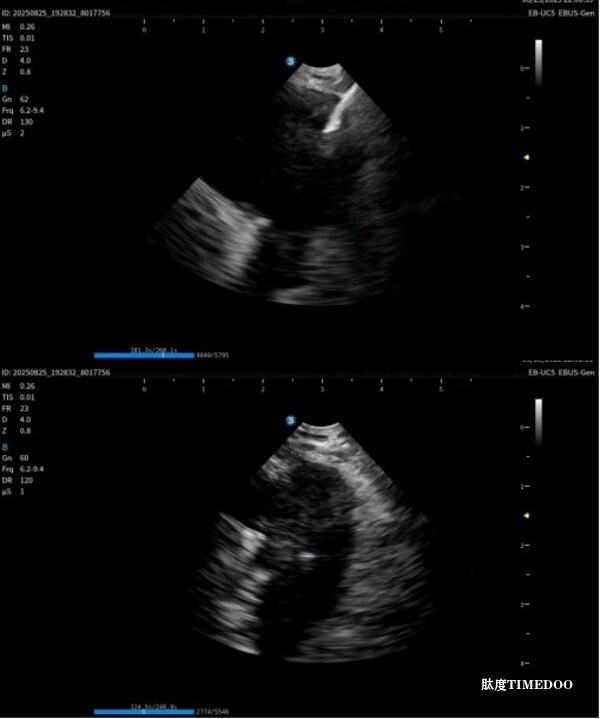

本次獲證標志著開立醫(yī)療實現國內首家在該領域做到產品系列最齊,功能最完備的超聲電子支氣管內窺鏡系統(tǒng):超聲電子支氣管內窺鏡+高清電子支氣管鏡+超聲微探頭+一體式超聲內鏡主機+分體式超聲內鏡主機,可滿足不同呼吸診療術式臨床應用需求。

作為在呼吸診療領域的重磅產品,本次在產品創(chuàng)新設計上和工藝技術上取得了重大突破,顯著提升了光學圖像和超聲圖像的質量,同時鏡體保持了良好的操作性,在鉗鏡比和視野角綜合參數可達到全球同類產品最佳性能。目前在臨床應用表現突出,取得了專家的認可和好評。

超聲電子支氣管內窺鏡憑借其”微創(chuàng)、精準、安全”的特點,已成為呼吸介入領域的核心技術之一。開立醫(yī)療全系列產品全面上市可為肺部腫瘤、縱隔病變提供管內清晰光學影像,管外高清聲學斷層組織及血流影像,提供精準可視化介入操作,為疾病的診斷提供更精準、更安全、更高效的一體化診療解決方案。